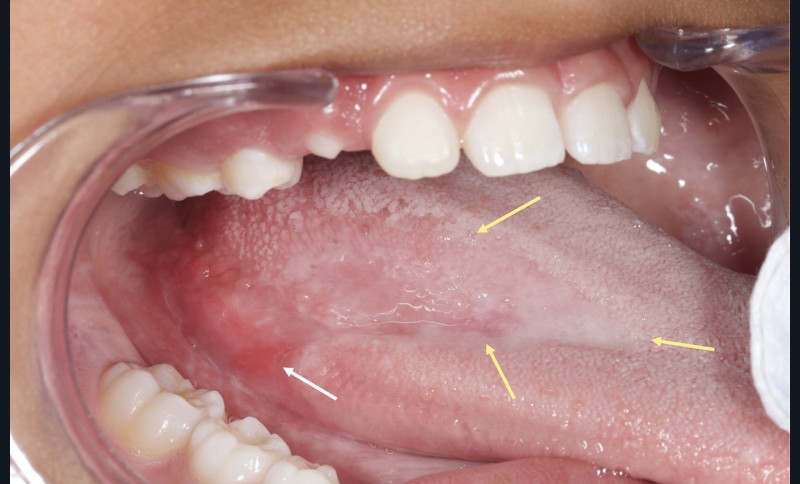

D’emblée, l’examen endobuccal met en évidence la présence d’une lésion linguale sur la face dorsale postérieure droite de la langue, bien délimitée, légèrement érythémateuse, d’aspect vernissé et atrophique avec altération ou perte des papilles. Cette plage s’étend sur 8 cm environ et rejoint une zone érosive, de plusieurs millimètres, située sur le bord de la langue. En outre, l’examen clinique révèle la présence de lésions blanches, d’aspect réticulé, au niveau de la face interne postérieure des joues, des vestibules postérieurs et du vermillon labial inférieur droit. Du côté droit, les lésions jugale, du vestibule et linguale se prolongent en continuité. Les autres muqueuses orales apparaissent saines. Par ailleurs, la palpation des muqueuses atteintes est indolore et permet d’écarter la présence d’une induration. De même, la palpation des zones ganglionnaires cervico-faciales exclut une adénopathie. Enfin, aucune atteinte cutanée n’est notée au niveau des membres et du tronc, au niveau unguéal ou du cuir chevelu.